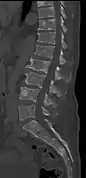

CT scan of the lower vertebral column in a man with multiple myeloma, showing multiple osteoblastic lesions: These are more radiodense (brighter in this image) than the surrounding cancellous bone, in contrast to osteolytic lesions, which are less radiodense.

The diagnostic examination of a person with suspected multiple myeloma typically includes a skeletal survey. This is a series of X-rays of the skull, axial skeleton, and proximal long bones. Myeloma activity sometimes appears as "lytic lesions" (with local disappearance of normal bone due to resorption). And on the skull X-ray as "punched-out lesions" (pepper-pot skull). Lesions may also be sclerotic, which is seen as radiodense.[47] Overall, the radiodensity of myeloma is between −30 and 120 Hounsfield units (HU).[48] Magnetic resonance imaging is more sensitive than simple X-rays in the detection of lytic lesions, and may supersede a skeletal survey, especially when vertebral disease is suspected. Occasionally, a CT scan is performed to measure the size of soft-tissue plasmacytomas. Bone scans are typically not of any additional value in the workup of people with myeloma (no new bone formation; lytic lesions not well visualized on bone scan).